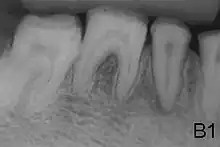

X-ray showing lack of enamel opacity and a pathological loss of enamel in patient with amelogenesis imperfecta

Preventive and restorative dental care is very important as well as considerations for esthetic issues since the crown are yellow from exposure of dentin due to enamel loss.[5] The main objectives of treatment is pain relief, preserving patient's remaining dentition, and to treat and preserve the patient's occlusal vertical height.[19]